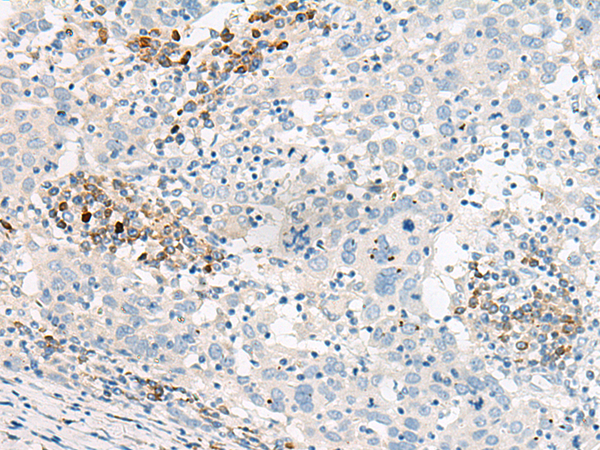

IHC positive control:

IHC Recommend dilution:

30-150